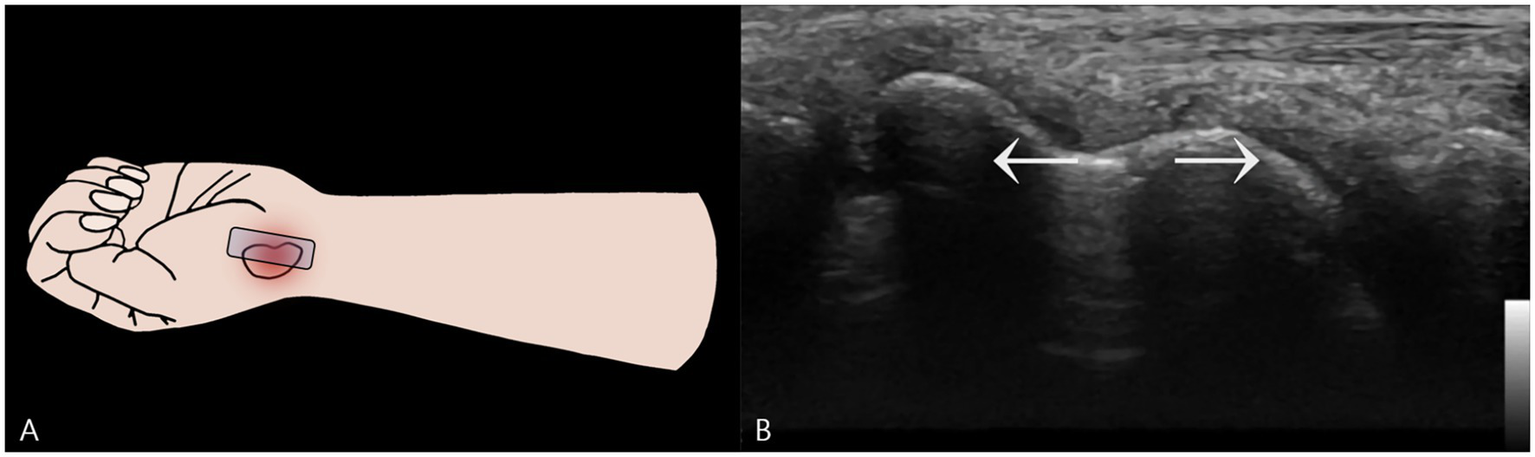

To assess functional stability, a dynamic examination was performed. A dynamic stress maneuver is defined as a gentle, controlled “heel-toe” probe rocking that applies focal pressure across the fracture while maintaining a longitudinal view, used to elicit real-time widening of the fracture gap as evidence of mechanical instability (Figure 3). With the wrist in this position, the examiner applied this controlled maneuver. A definitive fracture line, visualized as a hypoechoic cortical breach, was identified. The purpose of this maneuver was to apply shear stress across the fracture site to challenge its integrity. In real-time, this stress resulted in a visible widening of the hypoechoic fracture gap, providing unequivocal evidence of micromotion and confirming the diagnosis of a mechanically unstable fracture (Supplementary Video S1).

Figure 3

Dynamic Stress Examination of the Scaphoid Waist Fracture. (A) Schematic illustration showing the placement of the ultrasound probe longitudinally over the scaphoid waist. Focal pressure is applied directly onto the distal fragment using a “heel-toe” maneuver to assess for instability. (B) A two-dimensional ultrasound image captured during the application of dynamic stress. This image provides definitive evidence of mechanical instability by demonstrating a visible widening of the hypoechoic fracture gap.